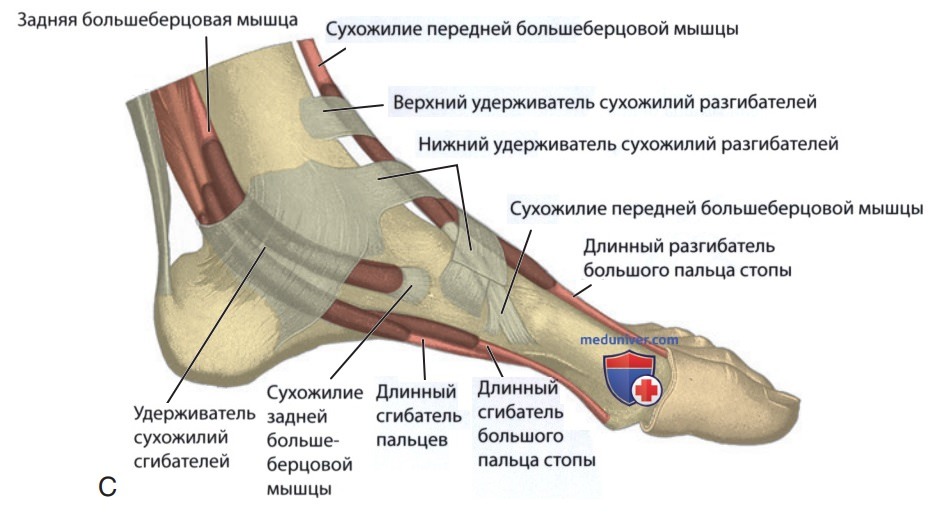

Анатомия голеностопа: Сухожилия и их строение